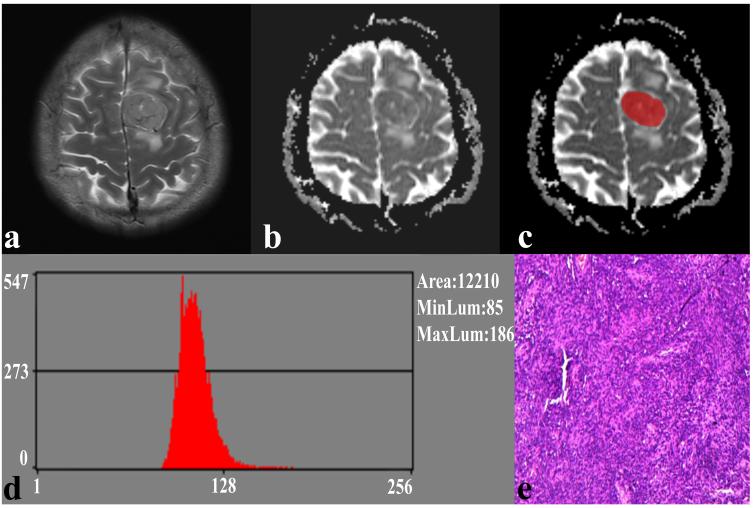

Preoperative diffusion-weighted imaging datasets of 24 SFT and 28 TM patients were used to extract whole volume ADC histogram parameters (including variance, skewness, kurtosis, as well as mean, 1st (AP1), 10th (AP10), 50th (AP50), 90th (AP90), and 99th (AP99) percentiles of ADC) using MaZda software by two experienced neuroradiologists (with 25 and 7 years of brain MRI experience, respectively) in a blinded way (Fig.1 and 2). The independent t-test or Mann–Whitney U test was used to compare the differences in ADC histogram parameters between SFT and TM. Receiver operating characteristic curves were generated to identify the performance of significant ADC histogram parameters. Spearman’s correlation coefficients were calculated to explore the correlations between these parameters and the Ki-67 expression.

Fig. 1. A 41-year-old male with SFT. (a) The axial T2WI image shows an inhomogeneous lesion on the left side of the falx cerebri. (b) The lesion shows an uneven low signal on the ADC image. (c) The lesion covered ROI on the ADC image. (d) Histogram of the ROI. (e) Pathological analysis confirms SFT (hematoxylin and eosin, ×100).